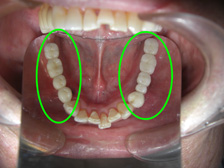

| 治療前 | 治療後 |

|  |  |

| 治療前 | 治療後 |

|  |  |

| 治療前 | 治療後 |

治療前

治療中

治療後